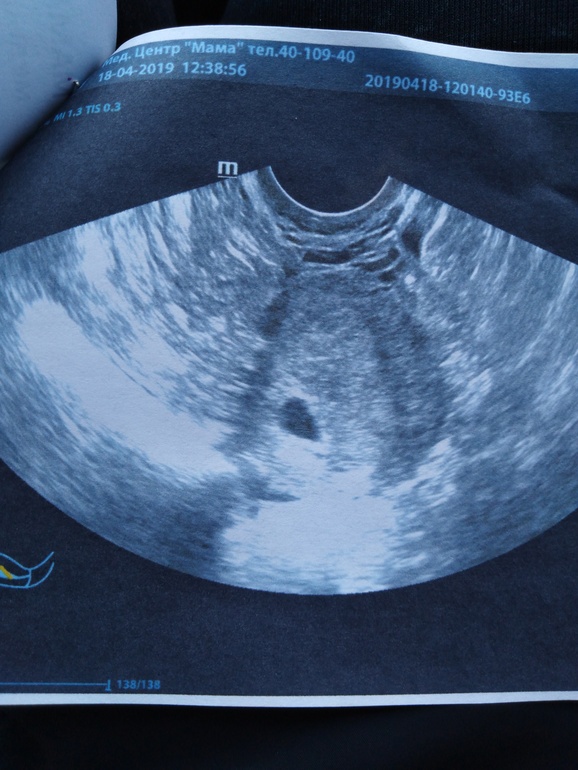

Переживала очень о внематочной, так как живу в городе, где врятли помогли бы, если бы лопнула труба, сделала только что УЗИ и увидела свою бубочку ❤️... Наше первое фото на память...

Я решила не терпеть и узнать где бубочка, а то при малейшем дискомфорте лезла внематочная в голову) теперь на одну проблему меньше)))